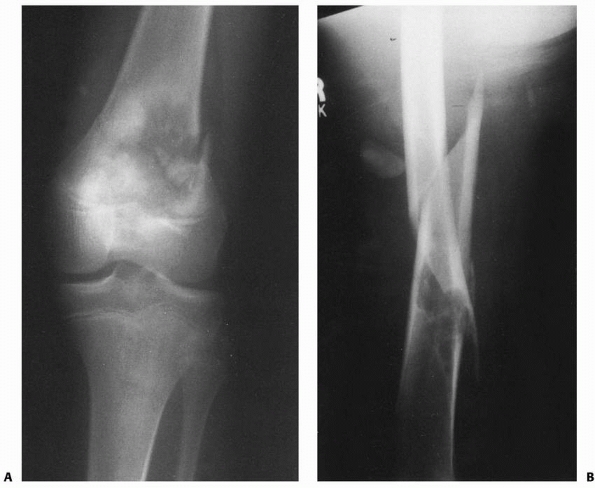

Pathologic fractures may occur in patients with neoplasms, most often

benign lesions such as nonossifying fibroma, aneurysmal bone cyst,

unicameral cyst, or eosinophilic granuloma. Although pathologic femoral

fractures are rare in children, it is essential that the orthopaedist

and radiologist study the initial injury films closely for the subtle

signs of primary lesions predisposing to fracture, particularly in

cases of low-energy injury from running or tripping. X-ray signs of a

pathologic fracture may include mixed lytic-blastic areas disrupting

trabecular architecture, a break in the cortex and periosteal reaction

in malignant lesions such as osteosarcoma, or better-defined sclerotic

borders with an intact cortex seen in benign lesions such as

nonossifying fibroma (Fig. 22-2).

![]() |

FIGURE 22-2 A. Femoral fracture through a poorly demarcated mixed, osteoblastic, osteolytic lesion—an osteosarcoma. B. Sclerotic borders of this lesion in the distal femur are typical of a pathologic fracture through a nonossifying fibroma.